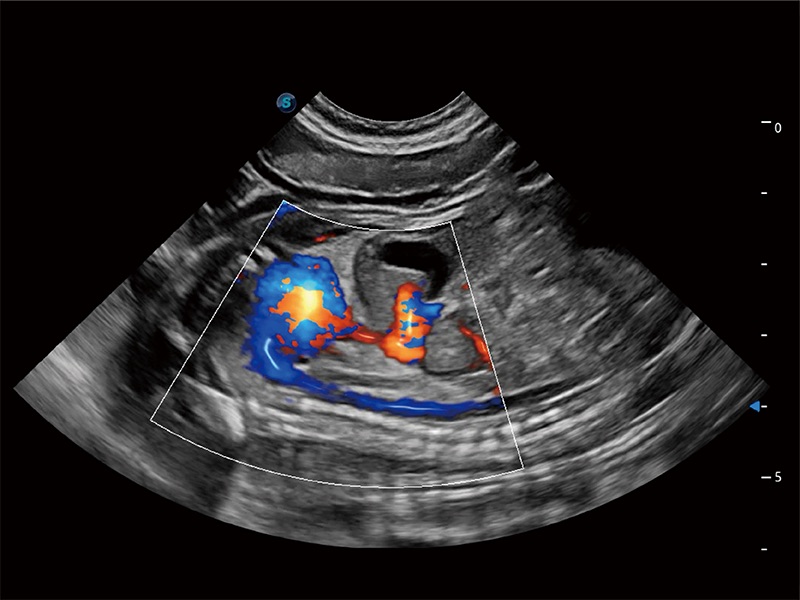

优异的基础图像

ProPet 80 全新的动物超声智能软件和丰富的探头群,为动物医生提供了高清晰度和精细分辨率的图像,无论在宠物、马科、畜牧还是实验室动物等应用中都可以轻松应对,为您的日常工作带来满意的体验。

(犬)二腔心血流